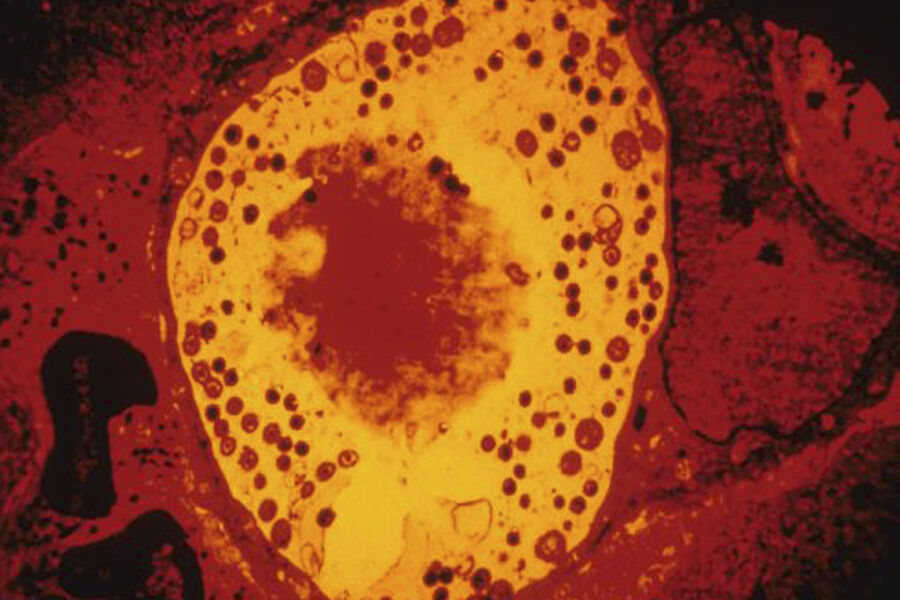

Анализ показал, что у пациентов с болезнью Альцгеймера в тканях сетчатки и головного мозга обнаруживались значительно более высокие концентрации хламидий. Это род грамотрицательных бактерий, виды которых относятся к облигатным внутриклеточным паразитам. Хламидии вызывают заболевания у человека, животных и птиц.

Чтобы разобраться в механизме, исследователи провели эксперименты на мышах. Они показали, что присутствие хламидий активирует хроническое воспаление, гибель нервных клеток и выработку бета-амилоида — токсичного для нейронов белка, накопление которого считается одной из центральных особенностей болезни Альцгеймера. В совокупности эти процессы ускоряли нейродегенерацию.